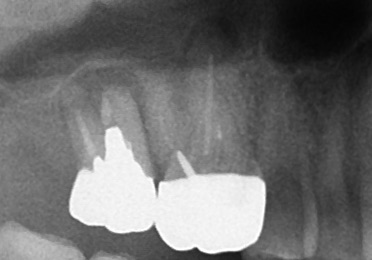

レントゲンを撮ってみると‥

(ちなみに6年前)

こちらはデンタルX線写真